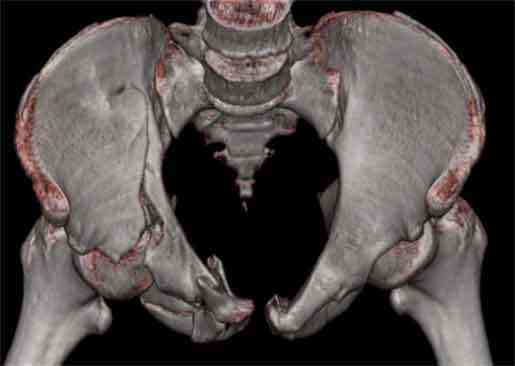

Не смог разглядеть на представленных картинках частичное повреждение левого КП, повреждение Денис1-2 справа? 3Д реконструкции в инлет и боковой проекциях убедительно не демонстрируют типа повреждения задних отделов тазового кольца(справа боковая масса скомпремирована), Наверное, у тебя есть возможность оценить тип перелома крестца по прямой проекции 3Д.

по Pennal et al.- латеральное компрессионное повреждение тип В(ротационно-нестабильное (внутренняя ротация), вертикально стабильное)

по Tile classif. тип В2-1 - частично стабильное повреждение с неполным разрывом задней дуги.

В данном случае 3D и корональные срезы КТ менее информативны, чем поперечные. Согласен с левосторенним минимальным повреждением КПС, но не смог уловить перелом крестца.

На 3D по линии перелома ацетабулум возможно сверху в подздошной кости уже есть сращение? или состояние перелома у молодых, после неполного (при пластической деформации) перелома.

По представленным материалам, мне кажется, перелом был передней колонны ацетабулум с минимальным вовлечением нагрузочной поверхности сустава, левосторенний повреждение КПС и лонных костей.